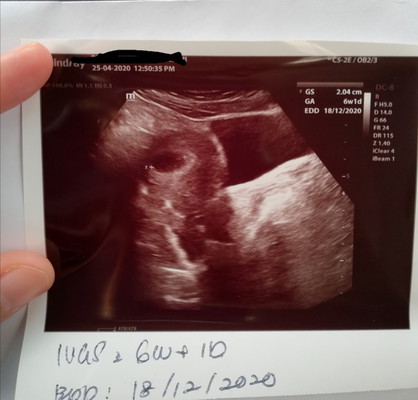

Sy pn ms scan ni br 6w1d..nmpk kantung jgk...tp doc ckp sy bkn 6w tp mayb 5w sb period sy irregular..so sy pikir positif je la still.awal xnmpk....28/4 ni scan semula...